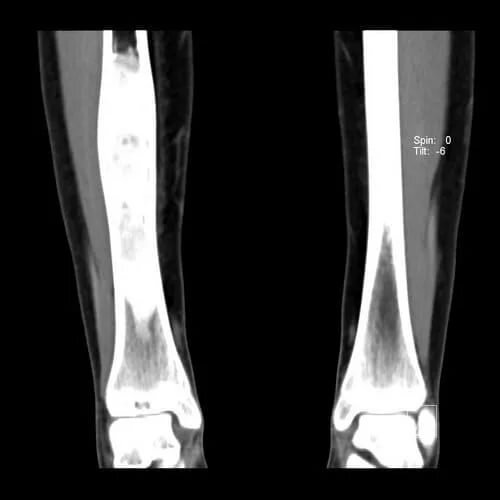

Если врач назначил вам КТ нижних конечностей, будьте уверены, что обследование на современном мультиспиральном компьютерном томографе покажет реальную картину состояния артерий и вен ваших ног. Компьютерная томография конечностей выполняется с использованием рентгеновского излучения для получения объемного изображения сосудов ног. Качественное исследование должно проводиться с контрастированием. Контраст вводится в организм пациента внутривенно в виде специального препарата с йодом. Процедура сканирования проходит безболезненно и комфортно для человека.

КТ сосудов нижних конечностей выполняется с контрастированием, когда в кровеносную систему пациента вводится рентгеноконтрастное вещество на базе йода. Больше никаких манипуляций пациенту не проводят. Обследуемый удобно располагается на столе томографа и соблюдает неподвижность в течение 10 минут, пока идет скрининг. КТ ног дает изображение сосудистой системы в трехмерных слоях и срезах. Полученные в результате обследования снимки позволяют оценить состояние сосудов нижних конечностей с любого ракурса и создать 3D реконструкцию.